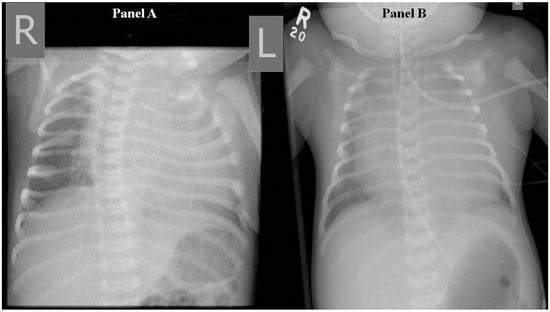

The patient was transferred to a tertiary paediatric hospital for paediatric neurosurgery and intervention radiology assessment, as this service was not available at our hospital. Following the transfer, a brain MRI was performed (Figure 3), and the patient underwent a coiling procedure to embolise the arterial feeders of the VGAM. In total, four coiling procedures were performed over a period of six weeks. Following the second of these, the patient was found to have hydrocephalus and underwent insertion of an external ventricular drain, which was removed after several weeks. Before discharge, an MRI of the brain demonstrated a reduction in the size of the VGAM and arterial collaterals, but also showed ongoing hydrocephalus and small bilateral infarcts in the corona radiata.

Figure 3.

T2-weighted sagittal MRI. The dilated galenic vein, namely, the median vein of prosencephalon (arrow), located midline in the cistern of velum interpositum, drains into the superior sagittal sinus (arrowhead).